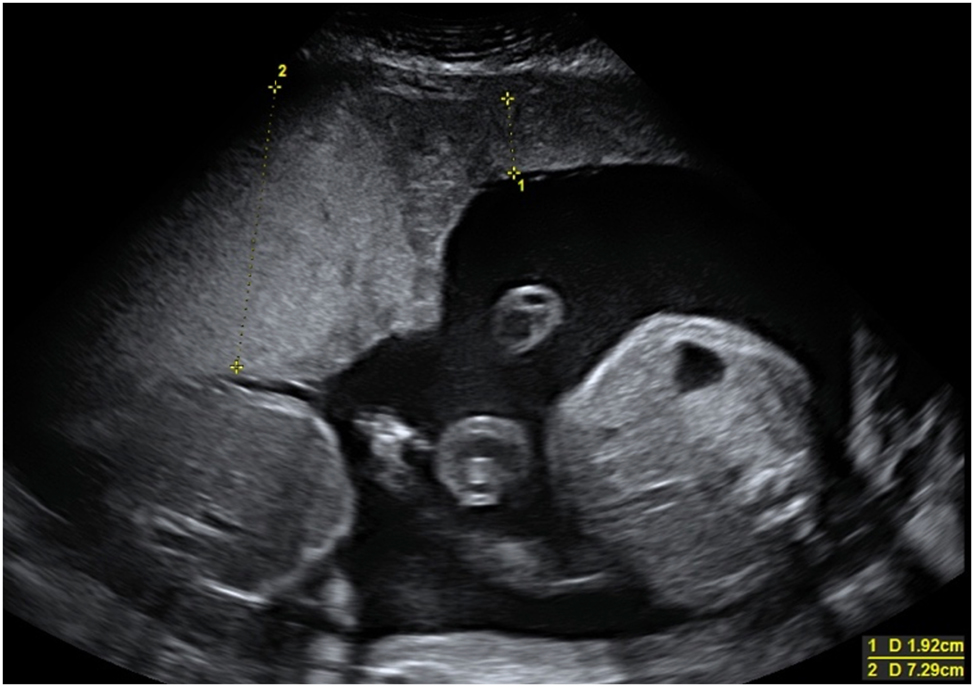

The Twin Reversed Arterial Perfusion Sequence (TRAP) is another complication occurring in monochorionic twins, with an incidence of 1 in 35.000 pregnancies [57]. This is the most extreme form of interfetal transfusion. Through an AA anastomosis of the monochorionic placenta, one twin (pumping twin) pumps blood retrograde via the umbilical cord into the arterial system of the other twin (parasitic co-twin). The latter develops hydrops fetalis at an early stage, the heart regresses and pronounced malformations of the upper half of the body (acardius acranius) are the result. The sonographically unremarkable pumping twin supplies the parasitic co-twin with blood, and this severe circulatory strain often leads to hyperdynamic heart failure, hydrops fetalis, and intrauterine death. With conservative management, approximately half of pumping twins survive [57]. The TRAP sequence can be diagnosed by experienced prenatal diagnosticians as early as the first trimester of pregnancy (Figure 7). After diagnosis at 12 weeks of pregnancy, 33 % of pumping twins in utero have died spontaneously and unpredictably by 16 weeks of pregnancy [58]. Spontaneous cessation of retrograde perfusion of the acardius occurs in approximately 20 % of cases [58]. In untreated cohorts, mortality rates exceeding 50 % have been reported for the pump twin, primarily due to progressive high-output cardiac failure and resulting preterm delivery [57], 59].

Figure 7:

Parasitic twin (acardius acranius) with absent heart and head, and retrograde umbilical artery perfusion.